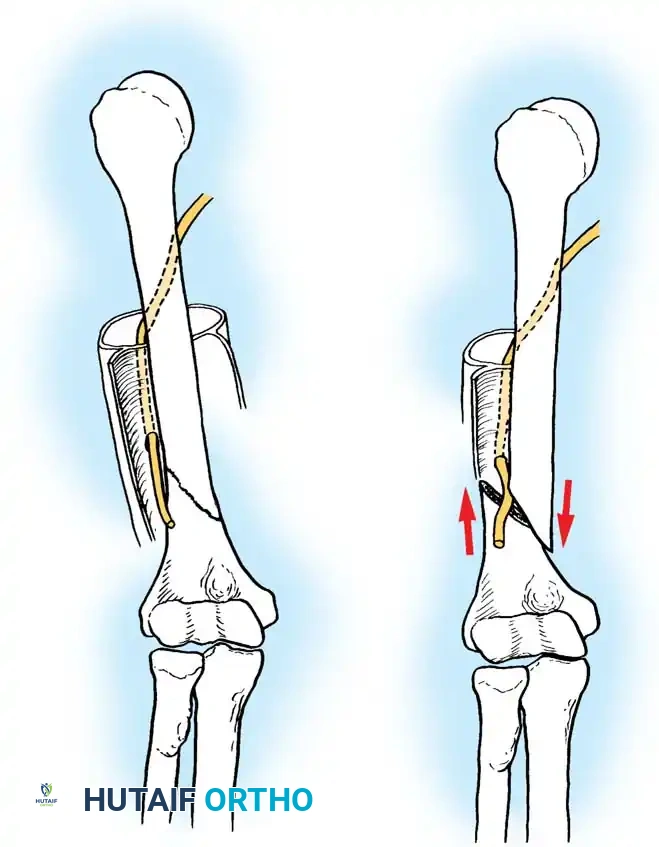

Minimally Invasive Plate Osteosynthesis (MIPO)

While MIPO has gained traction in lower extremity trauma, its application in the humerus is tempered by the risk of iatrogenic radial nerve injury. Cadaveric studies by Apivatthakakul et al. demonstrated that the plate sits an average of 3.2 mm from the radial nerve. Pronation of the forearm moves the nerve even closer (by 3 mm). Due to these risks, MIPO should be reserved for highly experienced surgeons.